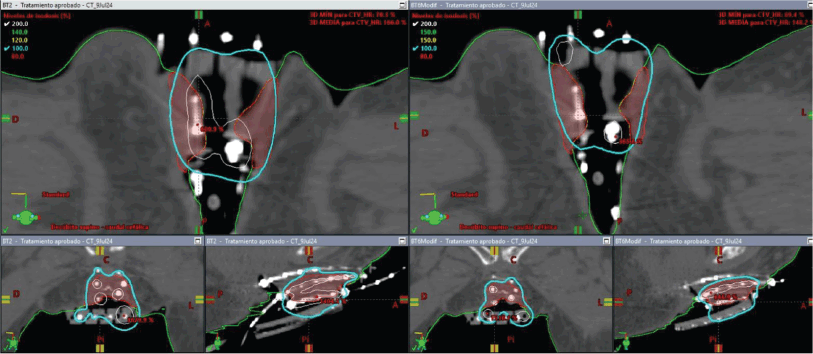

The initial plan suggested possible undercoverage in superficial regions of the tumour (Figure 3). Therefore, a custom silicone bolus containing four additional catheters was placed on the vulvar surface to enhance coverage of peripheral edges. A repeat CT confirmed improved D100 and D90 of the GTV while maintaining urethral dose constraints (Table 1, Figure 4).

Figure 3. Case 1. 3D treatment plan calculated on simulation CT for fraction #1. The position of the catheters and the dosimetric distribution in the axial, coronal and sagittal planes are observed, in addition to a 3D reconstruction. In light blue, the isodose of 5.7 Gy; in white, the isodose of 11.4 Gy.

Figure 4. Case 1. 3D treatment plan with bolus. The position of the catheters and the dosimetric distribution in the axial, coronal and sagittal planes are observed. On the left, fraction #2 to #5. On the right, fraction #6 to #8. In light blue, the isodose of 5.7 Gy; in white, the isodose of 11.4 Gy.